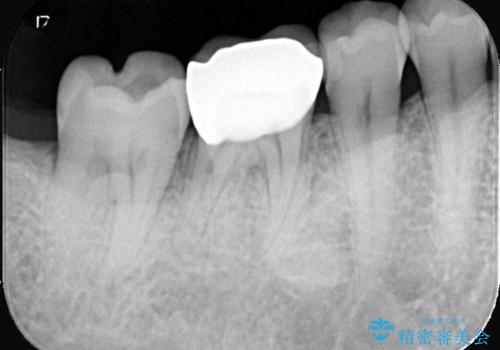

- 主訴:銀色の詰め物が取れてしまった。下の歯は笑うと見えるので、これを機に白くしたい。

保険適用のメタルインレーが脱離しており、歯冠色で審美性、適合性の良いセラミックインレーでのやり替えを提案しました。

メタルインレーが脱離した咬合面の窩洞内は、う蝕を除去し、セラミックインレーの厚みの担保とメタルタトゥー部分の除去を目的に形成を行いました。

インレーセット時はラバーダム防湿を行っています。